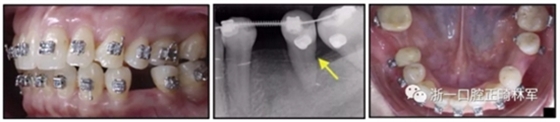

36歲;女性;尋求下頜左后方區(qū)域間隙管理的建議(圖1和圖2),通過治療獲得了良好的牙頜面效果(圖3和圖4)。她被診斷患有骨性I類和代償性牙性II類錯合畸形,并且上頜左側(cè)尖牙缺失(圖1和2)。大約七年前,由于不可修復(fù)的齲齒,拔除了下頜左側(cè)第一和第二磨牙(圖5)。37相鄰的第三磨牙向近中移動并傾斜入間隙,導(dǎo)致無牙頜間隙減小至約14 mm(圖2和圖5)。臨床和影像學(xué)評估顯示多發(fā)性齲損和在下頜右側(cè)567處有一不良的固定橋修復(fù)體(圖1和5)。此外,下頜左中切牙缺失,造成下頜中線向左側(cè)偏移約3 mm(圖1和圖2)。患者自訴,她的右上第一前磨牙和左上尖牙在13歲時由其家庭牙醫(yī)拔除,因?yàn)樗鼈儽蛔枞筋a側(cè)萌出(圖1)。上頜第二磨牙缺失(未知病因),并且相鄰的第三磨牙已經(jīng)轉(zhuǎn)移到第二磨牙間隙中。如補(bǔ)充材料所示,美國正畸學(xué)差異指數(shù)DI是28分。種植體部位(下頜左側(cè)和右側(cè)第一磨牙)由于復(fù)雜性得到額外4分(補(bǔ)充材料)。

圖1. 治療前面部和口內(nèi)照片

圖5. 治療前的側(cè)位片(上圖)和全景(下圖)的X光片